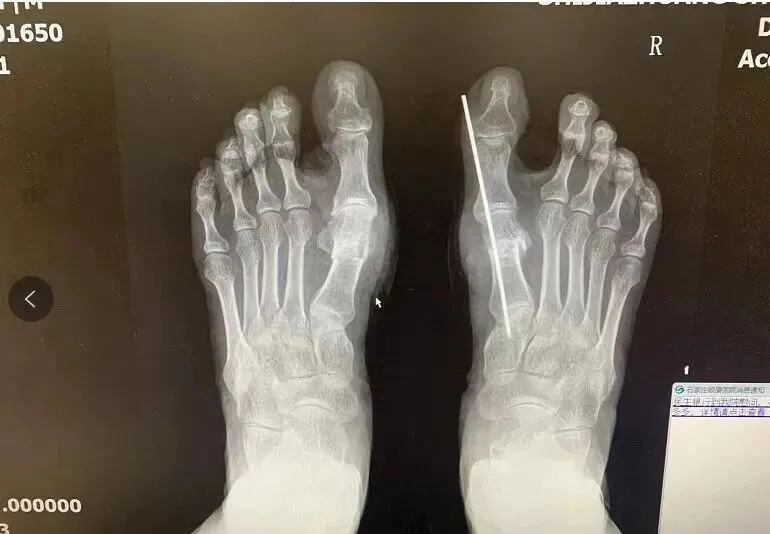

术后X光片参考